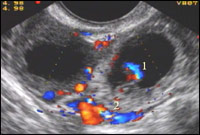

Ложное плодное яйцо – редко встречающийся признак, визуализируется как анэхогенное включение в полости матки, симулирующее полость амниона. Появление ложного плодного яйца связывают с гиперсекрецией трубчатых желез эндометрия или локальным скоплением крови в полости матки. Дифференциальная диагностика истинного и ложного плодовместилища основывается на его расположении в полости матки, форме и размерах, которые не соответствуют сроку гестации. Кроме того, ложное плодное яйцо визуализируется на границе смыкания стенок эндометрия, в то время как истинное плодное яйцо локализуется в толще какой либо стенки. В сроке 4-5 недель от дня последней менструации в истинном плодном яйце идентифицируется желточный мешок и элементы децидуальной оболочки, а в сроке 5-6 недель – определяется также эмбрион с признаками жизнедеятельности (табл. 1).

| Рисунок 6 |

|

| Эхокартина внематочной беременности |

В ряде случаев трубная беременность сопровождается образования кист желтого тела. По данным А.Н. Стрижакова, они встречаются у каждой шестой больной с эктопической беременностью.